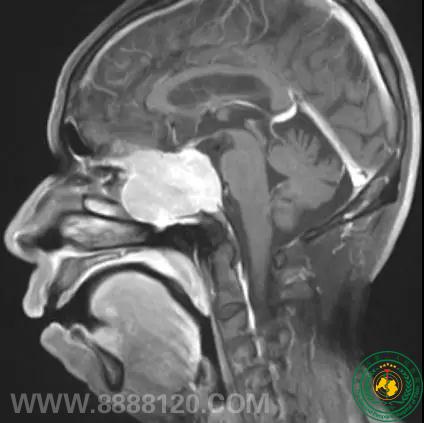

神经外一科完成四川省第一例经鼻神经内镜下蝶窦脑膜瘤切除术

神经外一科完成四川省第一例经鼻神经内镜下蝶窦脑膜瘤切除术18023